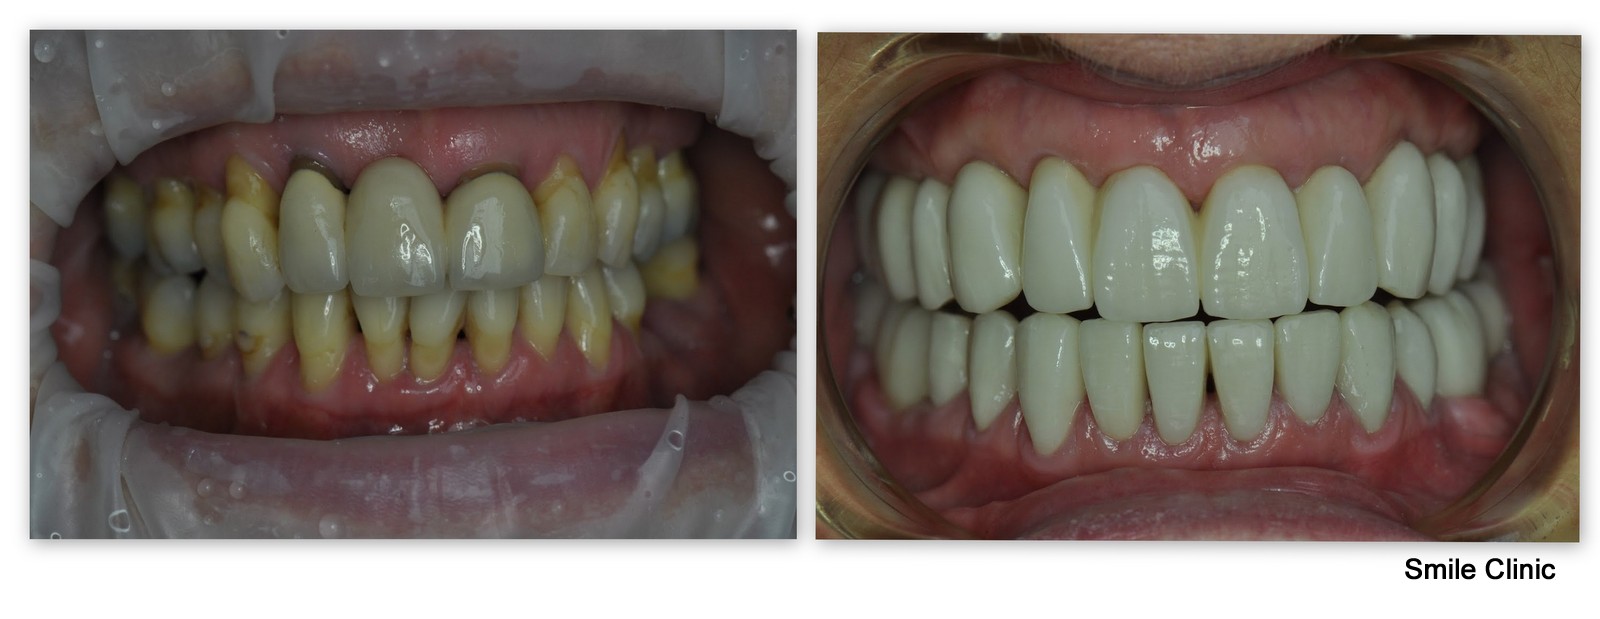

Mrs. Pamela from Manchester, UK, contacted us 2 months after her 50th birthday and her wish was to have all her teeth replaced with dental implants and dental crowns. She made a booking at our dental clinic for a consultation during which we made an X-ray and CT scan for her. Dr. Marek recommended the All on 6 treatment for her upper jaw. He suggested to keep her lower front teeth as they were in a good condition and place only 2 implants to her lower left back side and 2 implants to her lower right back side. After the consultation, Pamela decided to go back to the UK and take some time to make a decision.

We were happy when Pamela contacted us again and booked an implantation session with Dr. Marek in June. Our driver picked her up at the airport and drove her to our dental clinic in Piešťany. Before the doctor could fit the implants he had to extract 13 of her natural teeth. After that, in 5 hours, she already had her dental implants fit in her mouth. The doctor did socket preservation for all of her dental implants to make sure the implants will root to her jaw successfully.

After 90 days, Pamela came to Slovakia again and this time she brought her husband to support her 🙂 During this visit we took the impressions of her jaws/teeth. The doctor has also reshaped her remaining natural teeth on the lower front side to get them ready for treatment with dental crowns.

On her final visit, we fit the final implant crowns and also 9 zirconium dental crowns. Pamela left our clinic with a wide smile and she left us this pleasant testimonial: